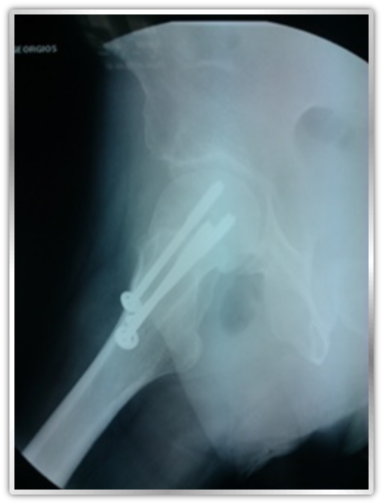

Ο ασθενής αντιμετωπίσθηκε συντηρητικά με αποφόρτιση σκέλους για 6 εβδομάδες και υπερβαρικό οξυγόνο με άριστο αποτέλεσμα κλινικό και απεικονιστικό. Η συγκεκριμένη περιοχή , εξαιτίας του κινδύνου επηρεασμού της αιμάτωσης της κεφαλής και πρόκλησης άσηπτης νέκρωσης , απαιτεί στενή παρακολούθηση. Η μη υποχώρηση των συμπτωμάτων με τη συντηρητική θεραπεία, η αύξηση του οστικού οιδήματος, φορά κατάγματος που παραπέμπει σε ασταθές κάταγμα είναι παράγοντες που συνηγορούν στη χειρουργική θεραπεία και σταθεροποίηση του κατάγματος με διαυχενικές βίδες.

Presentation: Case report bent cannulatead screw